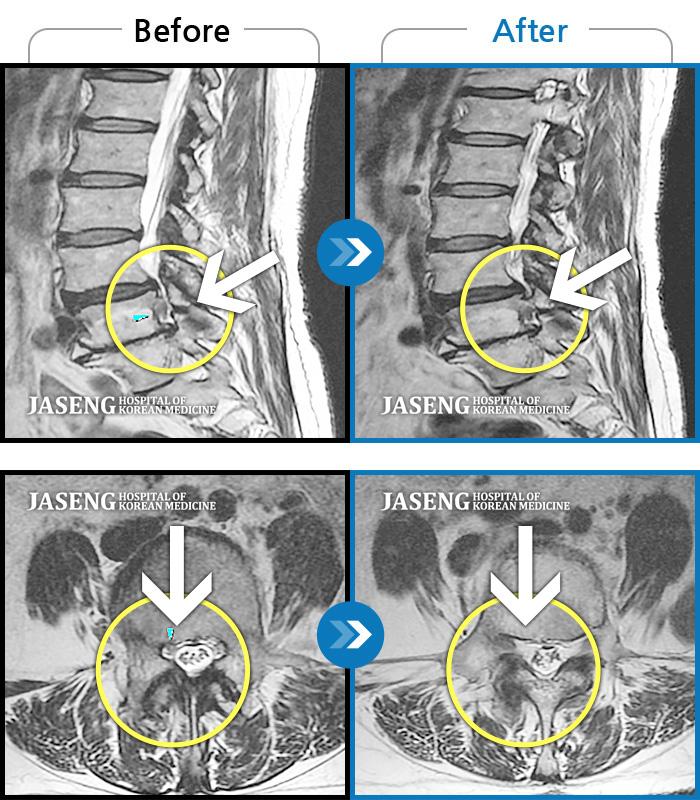

허리디스크

보라매 · 왕오호 원장

좌측 허리 통증 및 좌측 다리 저림

촬영시기

2016.05.21 ~ 2018.04.13

2018.12.28

조회수 675